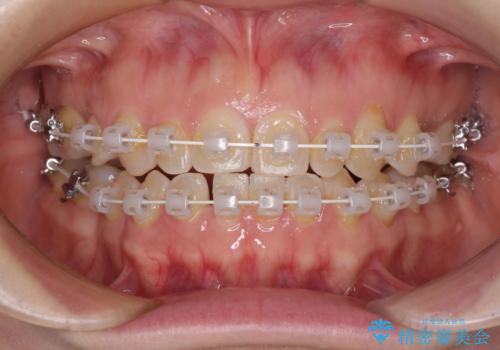

隙間の空いた歯列とボロボロの乳歯 インプラント治療と矯正治療

- 隙間の多い歯列や傾斜した奥歯、むし歯の酷い残存乳歯を気にして来院された患者様です。

歯列はワイヤー矯正にて改善することとしましたが、上下歯列にも隙間があったので、舌の突出癖を改善するトレーニングを徹底的に行うこととしました。